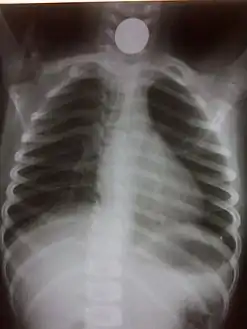

Chest radiograph showing a Venezuelan 25 cent coin lodged in the upper esophagus of a 9-year-old girl.

A coin seen on AP CXR in the esophagus

If the person who swallowed the foreign body is doing well, usually an x-ray image will be taken which will show any metal objects, and this will be repeated a few days later to confirm that the object has passed all the way through the digestive system. Also it needs to be confirmed that the object is not stuck in the airways, in the bronchial tree.